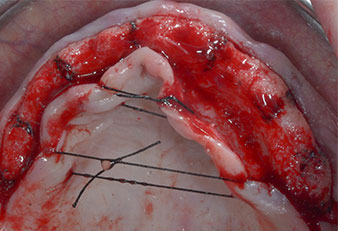

Three years later it was time for a maxillary denture of the same type. Based on CBCT planning sinus augmentation was avoided with the aid of short implants, and a surgical template was used to transfer the planned positions to the alveolar ridge (Figs. 1 and 2).

A flame-shaped, diamond-coated piezoelectric instrument (Piezomed I1) was used to mark the implant positions and to perform pilot preparation (Fig. 3). Care was taken to use an up and down movement, with reduced power, full irrigation and low pressure (below 300 g). Next a pilot instrument (Piezomed I2A/I2P) was applied for the initial 2 mm diameter enlargement of the implant sites (Fig. 4), followed by a 3 mm insert (Fig. 5).

Due to the relatively hard bone (D2) in this area, the 10 mm long implant sites at positions 11 and 21 were finalized with a 4 mm diameter rotary drill, in combination with a W&H WS-75 L surgical contra-angle handpiece, the W&H Implantmed implant motor and the optional W&H Osstell ISQ module. In contrast, due to the soft bone the posterior sites were prepared to a final 3 mm diameter using the Piezomed I3P instrument. The implants were finally placed transgingivally to osseointegrate for three months (Figs. 6-10). The existing denture was retained on four provisional implants (Fig. 8).